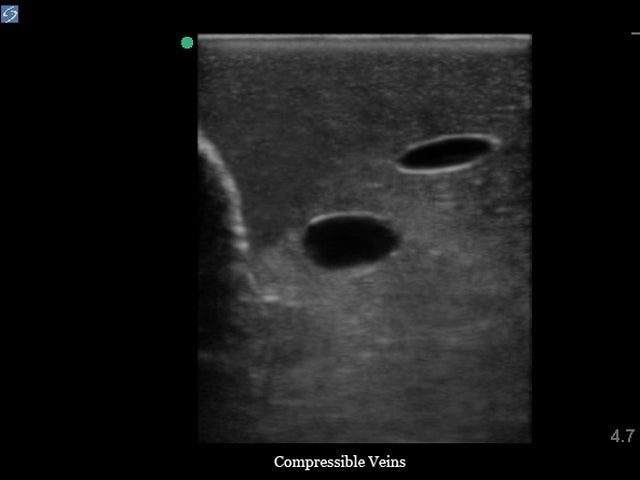

The vessels of our internal jugular central line ultrasound manikin offer extremely realistic performance and the arteries and veins can be differentiated by their accurate positioning, the arterial pulsatility and vein compressibility allowing users to teach and learn on this extremely realistic ultrasound phantom. Carotid arterial pulsation can be simulated using the included hand bulb and the internal jugular vein is compressible as you would expect to find in the human patient. The IJ central line trainer is prefilled with simulated blood; the arterial line contains red simulated blood while the venous system contains blue simulated blood, allowing for easy identification and positive feedback when the proper vessel is accurately accessed. Positive fluid flow in the vessels provides users with immediate feedback when the targeted vessel is accessed. Refilling the internal jugular training model is a quick and easy process using the included QuickFill™ access ports; high volume users can also attach an IV bag of ultrasound refill solution to the luer lock located on the QuickFill™ Tube allowing for continuous filling of the venous system.

- Veins are compressible using mild pressure

- Anatomically correct ultrasound model includes the carotid artery and internal jugular vein (IJ)